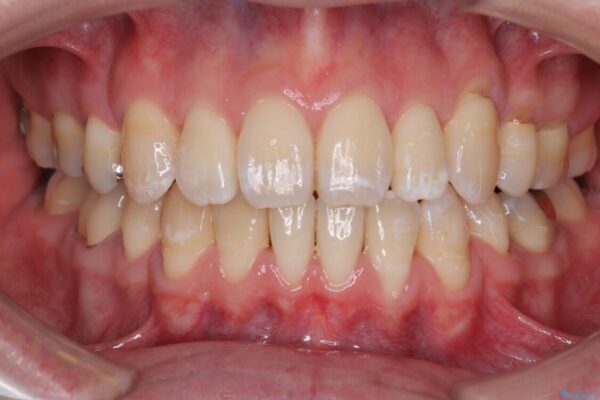

治療後

• 口元の突出感を改善!目立ちにくいワイヤー矯正で自信を持てる自然な横顔に 治療後画像